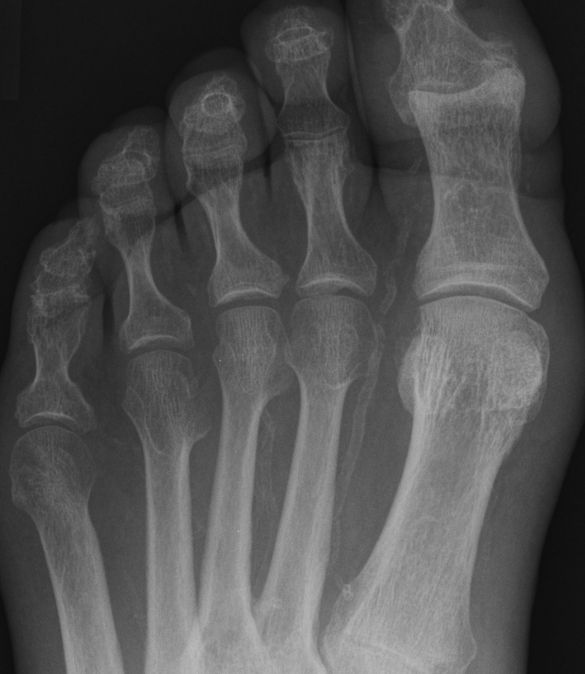

| Arteriae metatarsae dorsales | Entspringen aus der Arteria arcuata. Distal bilden

sie je 2 Arteriae digitales dorsales. Durch Verkalkung ist der Gefäßverlauf

ohne Kontrastmittel erkennbar.![]() | ||